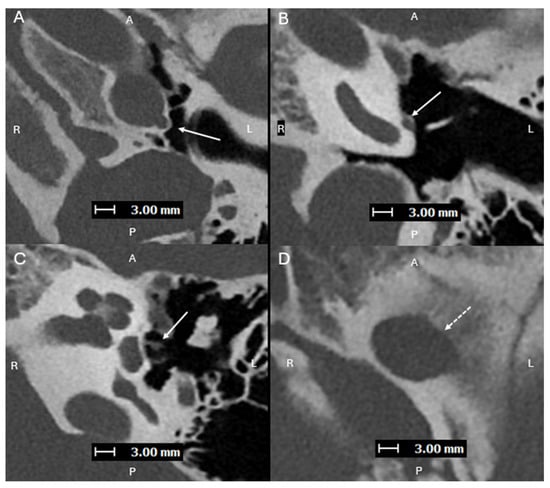

Figure 2. Axial images (superior to inferior (AD), with A, P, L, R for orientation donating anterior, posterior, left, and right respectively) from a PCD-CTA study—with UHR mode (Collimation 120 × 0.2 mm), Tube voltage (120 kVp), slice thickness/increment (0.2/0.2 mm), and sharp Kernel (Hv56) with Quantum Iterative Reconstruction (3)—demonstrating an aberrant L ICA (solid arrows) within an enlarged ITC (dashed arrows). Aberrant ICA are congenital vascular anomalies that occur from the involution of the cervical portion of the ICA, which leads to enlargement of the normally small collateral inferior tympanic and caroticotympanic (hyoid) arteries [1]. The segment most noted as the aberrant ICA is the inferior tympanic artery [2]. The inferior tympanic artery is a branch of the external carotid artery, usually the ascending pharyngeal artery, which extends through the inferior tympanic canaliculus (ITC), and is enlarged in the setting of an aberrant ICA [3]. As this artery courses along the cochlear promontory (via the ITC), no carotid plate separates the vessel from the middle ear cavity, and the vessel appears as a vascular retrotympanic mass on exam. It is very important to recognize an aberrant ICA on imaging. Accurately describing the presence of this aberrant vessel is important to help prevent iatrogenic injury during intervention of the middle ear. While typically asymptomatic in some cases, it can present with hearing loss and sometimes pain [4,5]. An aberrant ICA is commonly included in the differential diagnosis for vascular middle ear masses with other entities such as lateralized ICA, dehiscent jugular bulb, aneurysm of the petrous ICA, glomus tympanicum tumors, and glomus jugulare tumors [6,7].